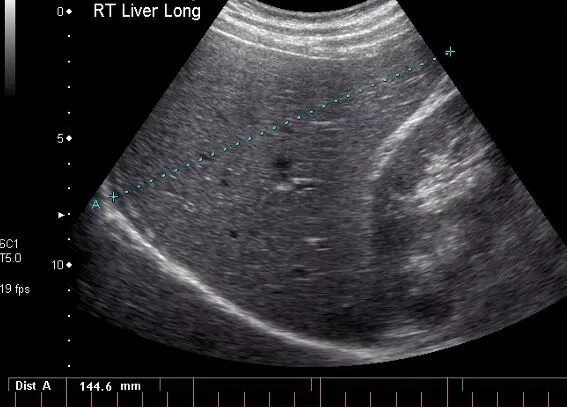

Узи шип